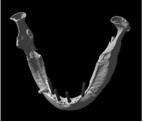

これは入れ歯を長年使い続けたことによって、歯を支える骨が溶けてしまっている患者さんのCTデータ三次元立体構築画像です(写真②)

入れ歯を長年使い続けていたために顎の骨の厚みがこんなに薄くなってしまいました

こちらは通常の人の顎の骨です(写真①)

通常の人の骨です。矢印先の丸く見えているのが下顎の中にある下歯槽神経の出口(オトガイ孔)です

この写真を見てお分かりのように同世代の人でも入れ歯を使っている人と入れ歯を使っていない人では、

顎の骨の高さ厚みが違うのです。

顎の骨の高さ厚みが違うということは、つまり、

顔貌(かおかたち)も大きく違ってくるということです。

下顎の中に丸い穴(矢印のところ)が見えると思います。

これは下歯槽神経といって下顎の中で一番大きな神経が骨の外にでてくる穴(オトガイ孔)です。

通常は写真①の方のようにちょうど骨の高さの真ん中ぐらいに位置します。

次に写真②をご覧下さい。

本来骨の高さの中央部分にあるはずの穴が上に向いて開いています。

つまり大きな神経や血管はとても大切なので、本来骨の奥深くに埋まって保護されているのです。

しかし、骨が大幅に溶けてしまって大きな神経が歯茎直下にまで出てきてしまっているのです。

歯があるときから神経が上にでているということは考えられませんので入れ歯を何年も使っていたために

本来骨の中にある神経のところまで骨吸収が起こったと考えられます。

神経が骨よりも上に出ていて入れ歯でこすられる状態ですので、

入れ歯を入れただけでも飛び上がるほどの痛さです。

白黒の立体画像では骨の高さや厚みと、神経の出口、歯の形などが分かりますが、

神経がどんな走行をしているかはわかりません。

そこで、詳しく骨の中の状態を見るためにはCTデータ3D立体構築画像変換検査をしていきます。

この検査によって3次元的に対象部の形態や位置関係をさらに詳しく知ることができます。

これは骨が溶けて神経が露出している状態です

この検査によりどこに重要な神経が通っているか一目瞭然です。